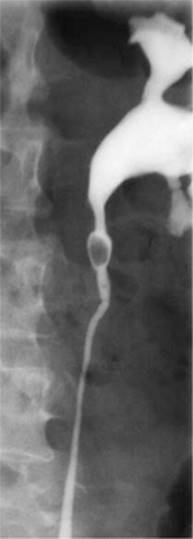

Prior to the popularity of CT for diagnosis, which has the advantages of high sensitivity, speed, lack of contrast administration and ability to detect other intra-abdominal pathologies, intravenous urography (IVP) was used to confirm the diagnosis of urinary obstruction, with demonstration of the causative calculus, either as a radio-opaque shadow in line with the ureter or as a radiolucent filling defect (Figs 9.4a-c), or showing a dilated upper urinary tract as the aftermath of a stone that has passed. IVP is now rarely performed in most emergency departments but is a useful adjunct if the diagnosis is equivocal. Ultrasound can be helpful in excluding other intra-abdominal and pelvic lesions or to demonstrate and serially monitor upper urinary tract dilatation due to obstruction. Ultrasound is thus of particular value in children, in whom repeated X-rays should be avoided. Renal colic with symptoms and signs of pyelonephritis (fever, systemic toxicity) always requires urgent imaging. An obstructed and infected kidney requires urgent relief, whereas obstruction in the absence of infection can be observed over the course of a week or more without likelihood of renal parenchymal damage.

Figure 9.4c IVP demonstrating proximal ureteric stone

Reproduced with permission from John Kourambas